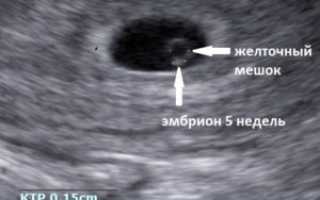

Срок, когда в плодном яйце появляется эмбрион, это третья неделя с момента оплодотворения. В это время он похож еще не на ребенка, а скорее напоминает просто полосочку в центре яйца.

Хороший врач на качественной аппаратуре сможет рассмотреть плодное яйцо, эмбрион в нем (он будет выглядеть как маленькая темная полоска длиной 3-5 мм), околоплодные воды; измерить его, оценить форму и прослушать сердцебиение эмбриона. Многоплодную беременность с уверенностью можно будет увидеть на более поздних сроках – примерно на 8-9 неделе.

В середине пятой недели специалист может рассмотреть внутри плодного яйца желточный мешок, который является первым источником питания развивающегося плода. Если на снимке УЗИ становятся различимыми плодное яйцо и желточный мешок, это также не является гарантией здоровой беременности, однако отсутствие последнего может говорить о серьезных патологиях развития эмбриона.